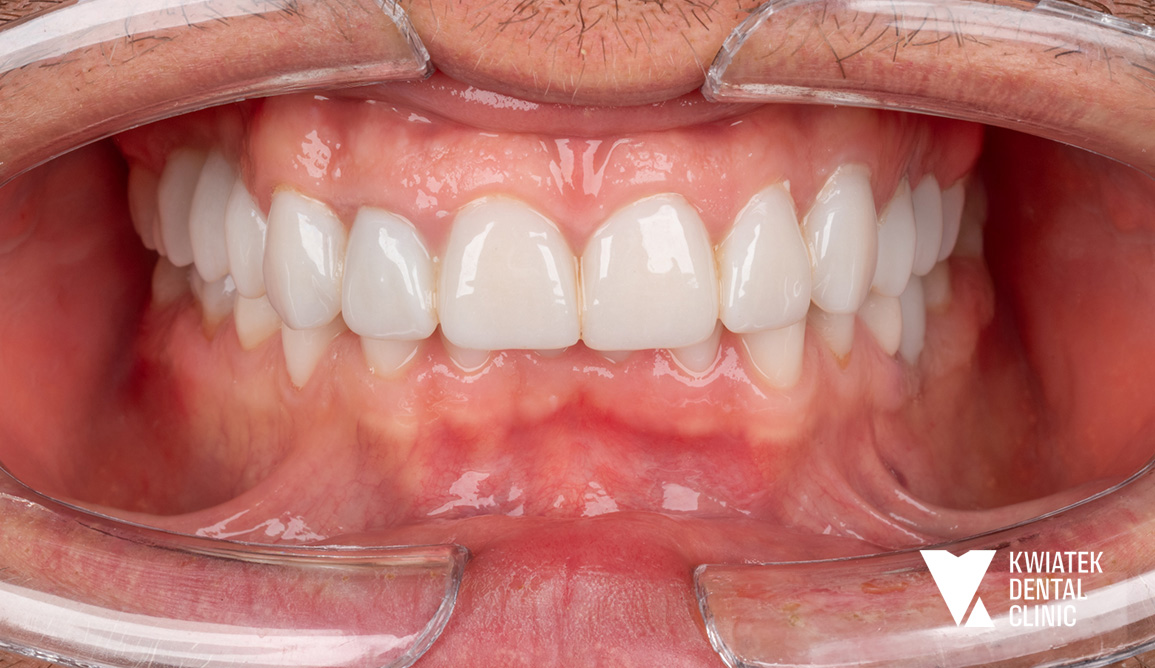

Uśmiech odzyskany – od kompleksowej terapii do naturalnego efektu!

Do naszej kliniki zgłosiła się Pacjentka, która w przeszłości była już leczona ortodontycznie. Mimo wcześniejszego leczenia wciąż zmagała się z brakiem górnej dwójki oraz przesuniętą linią pośrodkową, co wpływało zarówno na estetykę uśmiechu, jak i na prawidłową funkcję zgryzu.

Postawiliśmy na kompleksowe podejście – połączyliśmy leczenie ortodontyczne, implantologiczne oraz protetyczne. Dzięki temu udało się uzyskać harmonijny, pełen blasku uśmiech oraz prawidłowe warunki zgryzowe.

Efekt końcowy? Naturalna estetyka, piękny uśmiech i komfort, który daje Pacjentce pełną satysfakcję.